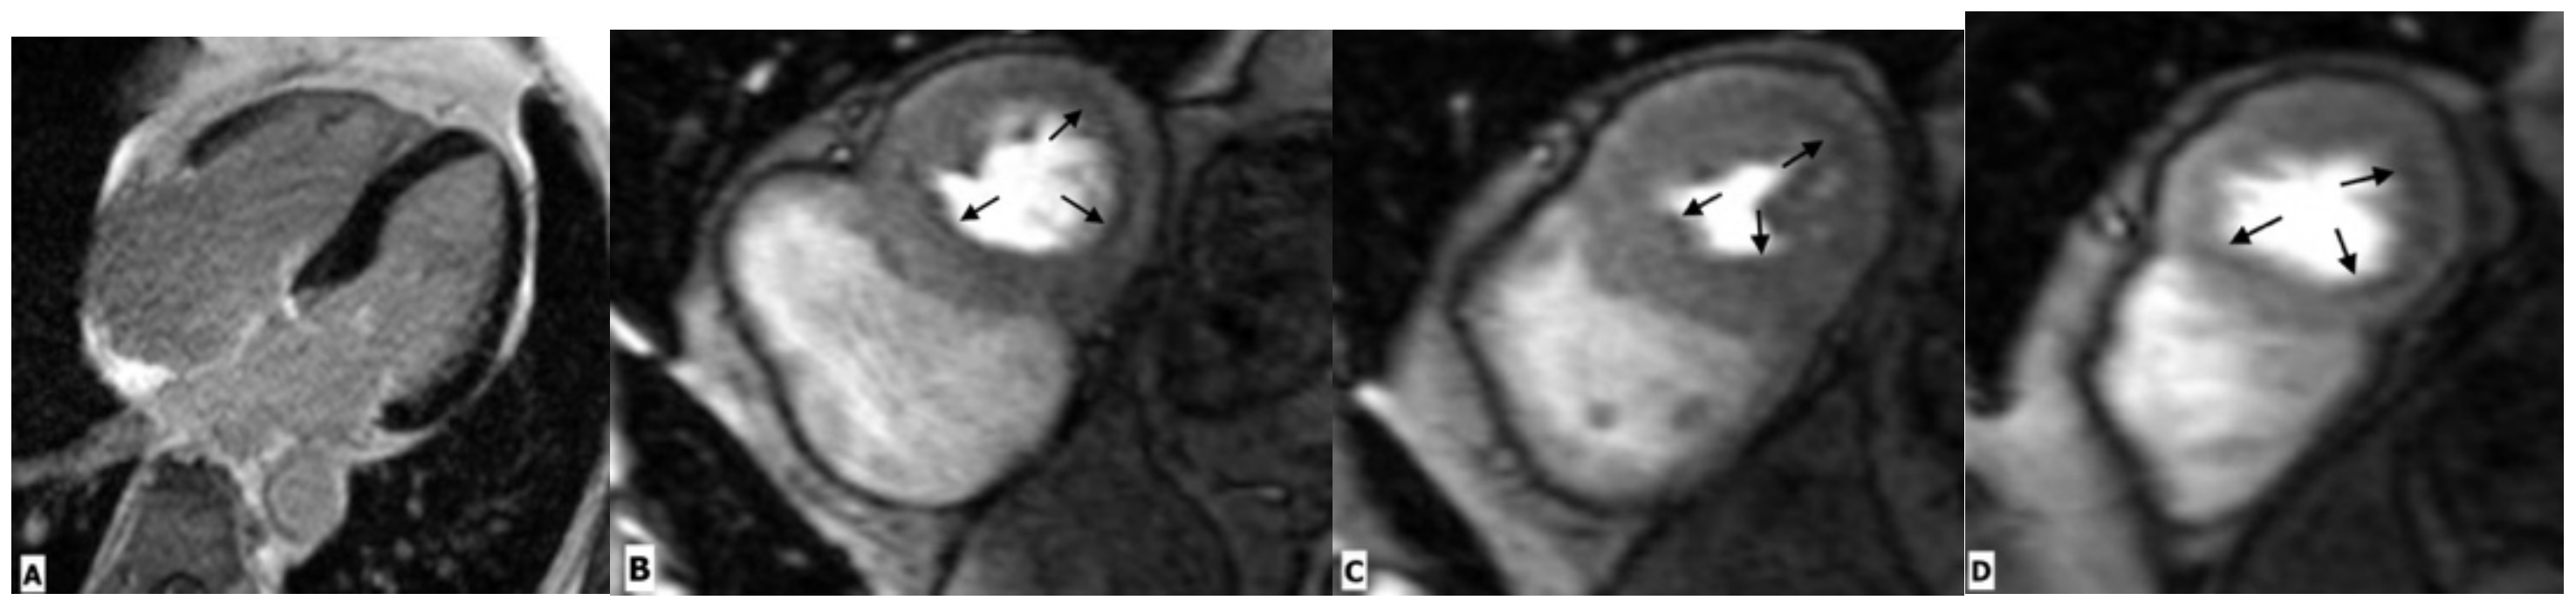

Figure 5.

Cardiac magnetic resonance imaging in a 65-year-old HIV-infected male patient with microvascular coronary dysfunction. (A) Mid-ventricular short-axis late gadolinium enhancement image showing no ischemic pattern. Stress CMR was performed via regadenoson administration. (B–D) Stress protocols images of three ventricular slices (basal, mid-ventricular, and apical slices) show diffuse subendocardial hypoperfusion (arrows) due to microvascular dysfunction. (E–G) Multiplanar reformatted contrast-enhanced computed tomography images showing the right coronary artery (RCA), left anterior descending artery (LAD), and left circumflex artery (LCx), respectively. RCA and LAD are normal without any atherosclerotic diseases. LCx shows focal mixed plaque causing minimal luminal stenosis (arrow).